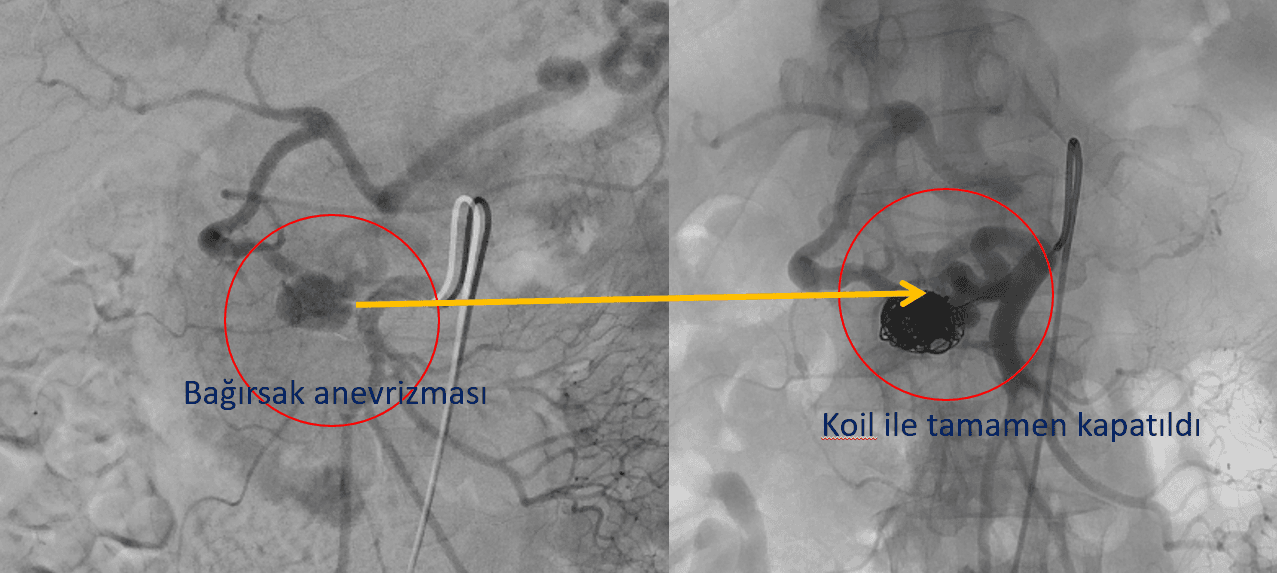

Aralıklı hafif şiddetli kanamaya neden olan bağırsak anevrizması anjiyoda tespit edilip ameliyatsız olarak tel sarmallarla kapatıldı